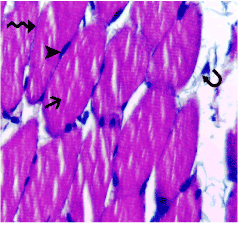

| Figure 2: Photomicrograph of a section in the skeletal muscle of a control rat (group I) showing: Normal histological architecture of the skeletal muscle fibers which appear transversely cut (arrow) with multiple, long and peripheral nuclei (arrowhead). Note the connective tissue endomysium separating the muscle fibers (wavy arrow) and the connective tissue perimysium separating the muscle bundles (curved arrow). Hx&E 400x. |